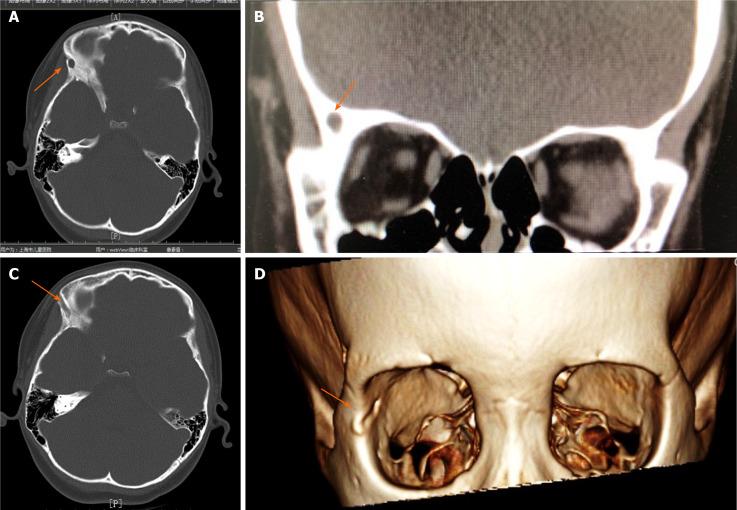

Three pediatric patients came to the clinic due to repeated infections of the skin and soft tissue of the temporal area. One patient presented with a temporal fistula that penetrated the temporal bone and reached the dura mater. Another patient presented with a temporal fistula that penetrated into the temporal muscle fascia. The third patient presented with a fistula that penetrated the lateral wall of the orbit and entered the orbit All patients underwent surgical fistula resection informed by preoperative computed tomography (CT) evaluation. Histopathological evaluation was also performed. All three patients were surgically treated successfully. Histopathological evaluations confirmed the fistula diagnoses in all three cases

For patients who have temporal fistulae with repeated infections, surgical treatment should be performed as soon as possible to prevent serious complications. CT can be very useful for preoperative evaluation. B-mode ultrasound examination and evaluation also have a certain auxiliary role.

三名儿科患者因颞部皮肤和软组织反复感染前来就诊。一名患者出现颞部瘘管,穿透颞骨并到达硬脑膜。另一名患者出现颞部瘘管,穿透至颞肌筋膜。第三名患者出现瘘管,穿透眶外侧壁并进入眼眶。所有患者均在术前计算机断层扫描(CT)评估的指导下接受了手术瘘管切除术。还进行了组织病理学评估。所有三名患者均手术治疗成功。组织病理学评估在所有三例中均证实了瘘管诊断。

对于患有颞部瘘管且反复感染的患者,应尽早进行手术治疗以预防严重并发症。CT对术前评估非常有用。B超检查和评估也有一定的辅助作用。